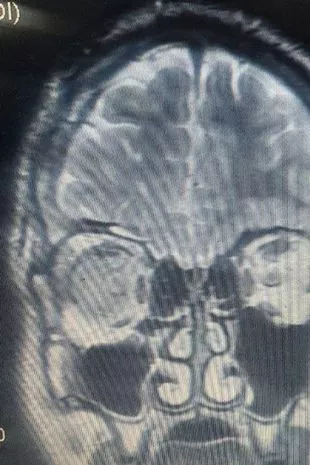

CT扫描显示他的右脑有突起(图片:ResearchGate网站)

他在重症监护室住了一个月,在此期间,扫描显示他的头骨骨折和脑膨出,并在他的鼻腔中发展。一层又一层的组织在骨折处突起,医生注意到他的大脑右侧区域出现了“明显的扩张”。